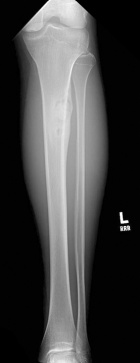

17 year old male c/o left shin pain. He is active in sports. First noted pain while running and with activities. Pain has been intermittent over 9 month period but more constant recently. A palpable lump is present on the left tibia which has not changed in size.